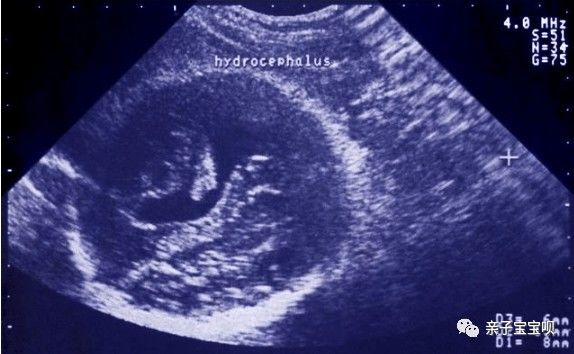

可是就在陈女士怀孕五个月去产检的时候,查出来胎儿脑积水。医生建议去大医院看看,怀着忐忑的心,一家人陪着陈女士到了省城大医院,结果是情况并不好,建议引产。